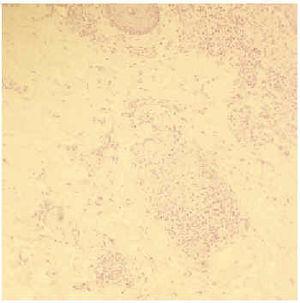

Una mujer de 56 años con antecedentes de histerectomía con doble anexectomía, cirugía de quiste de mama y quemaduras de tercer grado, por explosión de bombona de butano, en extremidades hacía 2 años. Acudió a consulta por presentar, en las cicatrices de estas quemaduras previamente estables, tumefacción con coloración eritematoviolácea y discreta sensación de quemazón al roce, de 2 meses de evolución. En la anamnesis refería sensación de astenia en los últimos meses sin otra sintomatología acompañante. A la exploración las cicatrices correspondientes a las quemaduras mostraban un aspecto hipertrófico e infiltrado, de coloración eritematoviolácea y consistencia firme, en extremidades superiores e inferiores (figs. 1-3). No existía afectación de las cicatrices secundarias a sus intervenciones quirúrgicas ni de la piel sana. El resto de la exploración física general, pulmonar y oftalmológica fue normal. En el estudio histológico de dos muestras cutáneas se observaron en dermis superficial y parte de dermis reticular, varios granulomas de células epitelioides con escasos linfocitos en la periferia y ausencia de caseificación central (figs. 4 y 5).

Fig. 4.--En dermis superficial y parte de dermis reticular se observan varios granulomas de células epitelioides.